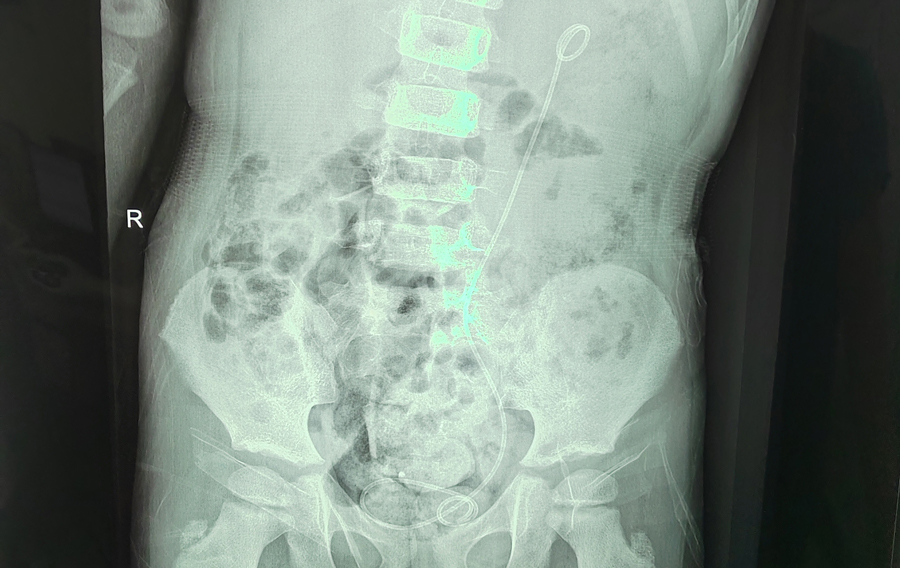

接下来是将剪断的输尿管进行吻合。由于切除了长息肉段的输尿管,此时再把存留的输尿管上下断端进行吻合,张力极大。能否吻合成功也是手术的关键。此时,手术室内静悄悄的,所有人的注意力都集中在腹腔镜的显示屏上,牵引、缝合、打结、置入输尿管支架管……在整个手术团队的精细操作和默契配合下,两段输尿管终于被成功吻合。当看到留置的尿袋里出现红色尿液时,说明吻合成功,输尿管通畅,所有人悬着的心才放了下来。术后,多多恢复得非常好,8月31日顺利出院。他的腰腹疼痛、肾盂扩张、肾脏皮质变薄症状会随着康复而明显缓解,后续定期复查即可。儿医人凭借这种不懈寻求疾病真相的精神,努力守护着儿童的健康。